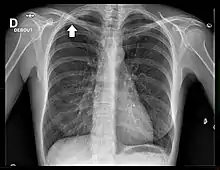

Radiographie thoracique

La radiographie thoracique est un examen de dépistage aisément accessible. Cependant, les tumeurs de l'apex de petite taille sont difficiles à visualiser en raison des superpositions osseuses de la clavicule et de la première côte[18].

Le cliché thoracique de face retrouve le plus souvent un simple épaississement de l'apex thoracique, ou bien une authentique masse pulmonaire englobant l'apex[20]. Une ostéolyse des côtes et du rachis est parfois visible[20].